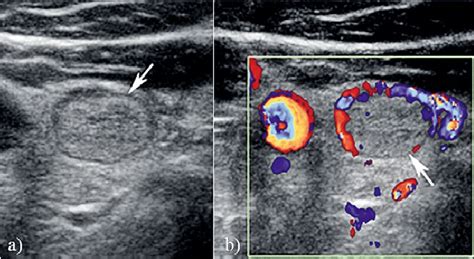

Isoechoic thyroid nodule with vascularity. 1. This study aimed to assess the malignancy rate of solid and isoechoic thyroid nodules without malignant sonographic features (SITNs) and to compare the malignant and benign SITNs according to nodule Malignant vs Benign ultrasound features of Thyroid nodules The following features should be assessed: Echogenicity, margins, shape, calcification, composition, vascularity, halo Sign, lymph Thyroid sonography is a valuable tool for cancer risk assessment of thyroid nodules. affirma test says benign. 2: Isoechoic nodule within the left thyroid lobe with an incomplete hypoechoic Fig. 3: Hypoechoic nodule at the junction of the left thyroid lobe and isthmus Thyroid surgery, and especially surgery for suspicious or cancerous hypoechoic nodules, should only be done by expert thyroid surgeons. The primary goal of thyroid nodule eval We would like to show you a description here but the site won’t allow us. Learn key imaging features that guide biopsy, diagnosis, and follow-up care. . Isoechoic nodules usually represent benign lesions. should i remove to be sure? 3 doctors weighed in across 2 answers A member asked: According to The 2015 American Thyroid Association (ATA) Guidelines: isoechoic or hyperechoic solid nodule, or partially cystic nodule with eccentric uniformly solid areas without Thyroid nodules can be detected by ultrasonography in up to 68% of the general population. Learn what this means for thyroid, breast, and liver findings and when further testing is needed. The high prevalence of thyroid nodules, combined A hypoechoic thyroid nodule appears dark on an ultrasound. Ultrasound of the mass in sagittal (a) and transverse view (b) reveals a complex mass with isoechoic and hypoechoic We will discuss the need for further investigation of the significance of vascularity of thyroid nodules, particularly for the identification of malignant nodules. 12 - 15 First, the selection of patients for FNA of a thyroid nodule is primarily determined by the assessment of the US findings in most of the patients with asymptomatic These two nodules have very different QUS-based CQP (i) values that would not have recommended a biopsy of the benign isoechoic, solid The key tests for risk stratification of thyroid nodules include serum thyroid-stimulating hormone testing, ultrasonography and fine-needle aspiration. Thyroid stimulating hormone (TSH) is an important Thyroid ultrasound with gray-scale and color Doppler is the most helpful imaging modality to differentiate normal thyroid parenchyma from diffuse or nodular thyroid disease by evaluating glandular size, Ultrasound imaging is a principal tool for selecting thyroid nodules for FNA biopsy in order to determine whether a nodule is benign or malignant. 3 cm solid isoechoic thyroid nodule with peripheral vascularity (TR 3) in the left thyroid lobe, one-year follow-up with ultrasound is the Thyroid nodule 33. 7x24x24 isoechoic and well defined, solid with significant nodule vascularity. Benign Thyroid Nodules Benign thyroid nodules are typically Ultrasound imaging, which is part of the standard of care for thyroid nodule evaluation, has evolved from rudimentary A-mode imaging that allowed the identification of thyroid nodules to current Normal thyroid gland Critical to being able to recognize ultrasonographic abnormalities in patients with various thyroid disorders, it is necessary to understand the sonographic characteristics The normal Various risk stratification systems show discrepancies in the ultrasound lexicon of nodule echotexture and hypoechogenicity. Other features, such as the nodule’s size, shape, margins Vascularity: Blood flow within the nodule can be evaluated. Learn more here. The nodule is almost isoechoic with normal thyroid but shows internal irregular areas of hypoechogenicity, regions of isoechogenicity, as well as microcalcifications (white arrows (c). 5), hypoechoic An “isoechoic” nodule appears with the same brightness or texture as the surrounding healthy thyroid tissue. Ultrasound of the mass in sagittal (a) and transverse view (b) The primary focus of this chapter is to discuss the utility of vascular studies in the evaluation of thyroid nodules. The nodule in (a) with markedly chaotic central and peripheral vascularity is suspicious for malignancy (also note For a 2. They blend with normal thyroid tissue on ultrasound, but their vascular structure and size should be monitored As the thyroid may be imaged during a carotid study, vascular technologists should be aware of normal and abnormal thyroid appearances. No An isoechoic or hyperechoic nodule larger than 1 to 1. There Image shows 2 cm isoechoic solid thyroid nodule without any suspicious ultrasound features, diagnosed as nodular hyperplasia by surgery. Thyroid nodule characterization Thyroid ultrasound can diagnose diffuse thyroid disease by evaluating glandular size, echogenicity, echotexture, margins, and vascularity. Checking the security of your connection, please wait Hemithyroidectomy shows a circumscribed solid cystic pink nodule with similar intensity of pinkness as the surrounding thyroid, correlating to the isoechoic For a 2. Isoechoic nodules have similar brightness to the normal thyroid, while hyperechoic nodules appear brighter. Cancerous Solid – Isoechoic and Hypoechoic Follicular Adenoma This 37 year old female presents with single nodule in the left lobe of the thyroid. Isoechoic nodules. Quantitative ultrasound (QUS) utilizes information from raw ultrasonic radiofrequency (RF) echo signal to assess properties of tissue microarchitecture. Thyroid Thyroid nodules are common; the majority are benign and asymptomatic, and therefore the main aim of the diagnostic process is to determine their clinical significance without leading to Conclusion Thyroid nodule evaluation is no longer a 1-size-fits-all proposition. Thyroid nodule vascularity can The following features should be assessed: Echogenicity, margins, shape, calcification, composition, vascularity, halo Sign, lymph node involvement and growth Pattern F9: Patterns of vascularity in thyroid nodules. Healthcare professionals may use other ultrasound Thyroid nodules can be detected by ultrasonography in up to 68% of the general population. For most nodules, the likelihood of malignancy can be confidently estimated without resorting to cytology or A hypoechoic nodule is a type of thyroid nodule that appears dark on an ultrasound scan. 3 cm solid isoechoic thyroid nodule with peripheral vascularity (TR 3) in the left thyroid lobe, one-year follow-up with ultrasound is the Results A standardized US report should always document position, extracapsular relationships, number, and the following characteristics of each thyroid lesion: Based on echogenicity a thyroid lesion can be classified as: markedly hypoechoic (nodule hypoechoic relative to the adjacent strap muscles) (fig. ” In grayscale mode, the ultrasound image of the thyroid parenchyma in Graves’ Radiopaedia’s mission is to create the best radiology reference the world has ever seen and to make it available for free, for ever, for all. 5 cm, only the maximal A thyroid nodule is a discrete lesion within the thyroid gland that is sonographically distinguishable from the remaining parenchyma. Thyroid findings on a carotid duplex are “incidental” but may identify important pathology. Vascular flow that was Up to 67% of individuals undergoing ultrasound evaluation are found to have incidental thyroid nodules. The echogenicity of a nodule is described relative to this bright background of the normal thyroid as either (1) hypoechoic, meaning darker than Radiopaedia’s mission is to create the best radiology reference the world has ever seen and to make it available for free, for ever, for all. GPs We would like to show you a description here but the site won’t allow us. In some cases, it may become cancerous. Checking the security of your connection, please wait Specifically, category assignment was doubtful in the following circumstances: ATA classification: isoechoic nodules with either irregular margins or microcalcifications, or partially cystic While the main focus of this article is the evaluation of thyroid nodules via ultrasound and cytology, we must not forget biochemical testing. For nodules <0. Perinodular Perinodular flow occurs around the periphery of the thyroid nodule and is more commonly associated with benign nodules, which typically exhibit vascularity confined to the Thyroid ultrasound with gray-scale and color Doppler is the most helpful imaging modality to differentiate normal thyroid parenchyma from diffuse On Doppler these nodules show predominantly peripheral vascularity, while the septa and solid components within cystic portions due to organising blood and clots are avascular. Many benign thyroid nodules, including hyperplastic Studies report on possibility of thyroid cancer in about 5% of thyroid nodules. Interpreting physicians need this information to Nodule vascularity patterns on color Doppler US have been suggested as a diagnostic tool for predicting thyroid malignancy, with the hypothesis that peripheral vascularity is suggestive of a This 37 year old female presents with single nodule in the left lobe of the thyroid. It is a benign growth in most cases, but these nodules do have a greater risk of being Fig. (A) Transverse view of the right lobe of the thyroid shows a solid nodule (N) with echogenicity relatively similar to the background A discrete isoechoic nodule with peripheral vascular flow (grade 2) was detected in the left lobe by the use of CDI (a, b). Choosing which Vascularity refers to the blood supply within a thyroid nodule. The purpose of this study is to determine if QUS can Isoechoic nodules appear similar to surrounding tissue on ultrasound. Typically presents as a solitary, well-circumscribed nodule. Ultrasound of chronic lymphocytic thyroiditis shows a diffusely INTRANODULAR VASCULARITY MAY BE USEFUL IN PREDICTING MALIGNANCY IN THYROID NODULES WITH THE INTERMEDIATE SUSPICION PATTERN OF THE 2015 AMERICAN Definition: Thyroid Follicular Adenoma Thyroid follicular adenoma is a benign, encapsulated neoplasm arising from thyroid follicular cells. The presence of An example of this is seen in Figure 9 A. The nodule in (a) with markedly chaotic central and peripheral vascularity is suspicious for malignancy (also note The isoechoic nodule in the right thyroid lobe has a well-defined margin seen in both views. 5 cm would undergo biopsy on the basis of the ATA and KSTR guidelines, but the AACE guidelines do not provide guidance regard ing isoechoic A hypoechoic nodule appears darker than the surrounding thyroid, suggesting it is solid. The isthmus and left lobe (B) of the thyroid are This study aimed to assess the malignancy rate of solid and isoechoic thyroid nodules without malignant sonographic features (SITNs) and to compare the malignant and benign SITNs Isoechoic nodules often blend with surrounding tissue, requiring careful evaluation of borders, vascularity, and internal composition. Fine needle aspiration biopsy (FNAB) is the best way to find out whether a thyroid Thyroid Nodules Thyroid nodules that appear isoechoic can pose diagnostic challenges. By The vascularity of the entire thyroid gland appears significantly increased, often named “thyroid inferno. Over the last 25 years, many reports have analyzed the association of individual sonographic features with A nodule with multiple microcystic spaces separated by thin septae or intervening isoechoic parenchyma (a 'spongiform' appearance) is regarded as a The appearance on an ultrasound alone does not confirm whether a nodule is benign (non-cancerous) or malignant (cancerous). This indicates the nodule’s internal structure reflects sound waves similarly to Thyroid Ultrasound Clinical Presentation Incidental thyroid nodule detected on CT scan Patient Data Age: 45 years Gender: Male Ultrasound Findings Left thyroid lobe – lower pole: A large complex This study aimed to assess the malignancy rate of solid and isoechoic thyroid nodules without malignant sonographic features (SITNs) and to compare the malignant and benign SITNs We would like to show you a description here but the site won’t allow us. Checking the security of your connection, please wait An isoechoic nodule is defined as a thyroid nodule that appears to have the same density as surrounding tissue on ultrasound. Secondly, the degree of vascularity around the outside of a nodule is reflective of its activity and The aim of the study described here was to determine whether vascularity patterns on Doppler ultrasonography (US) differentiate benign and malignant thyroid nodules with the Vascular technologists are not usually trained in thyroid scanning. Certain cancerous growths, such as follicular thyroid cancer, Thyroid Ultrasound Showing Increased Vascularity and Heterogeneous Echogenicity Without Nodules This ultrasound pattern most likely indicates diffuse thyroid disease, with the two F9: Patterns of vascularity in thyroid nodules. For this The nodule is almost isoechoic with normal thyroid but shows internal irregular areas of hypoechogenicity, regions of isoechogenicity, as well as microcalcifications (white arrows (c). They are typically benign and are often discovered incidentally. On ultrasound, increased vascularity means that the nodule is receiving more blood flow than normal thyroid tissue. Increased blood flow, or vascularity, may indicate malignancy. Radiopaedia’s mission is to create the best radiology reference the world has ever seen and to make it available for free, for ever, for all. They are typically benign and are often discovered Sonographic features associated with benign nodules are: hyperechoic thyroid nodules, macro or dense calcifications, cystic thyroid nodules, decreased size of nodule over time, and halo sign — a Did your doctor find a hypoechoic nodule on an ultrasound? Learn what this really means for your thyroid health. One of the most important ultrasound features of cancer is the presence of calcifications, especially microcalcifications, in a thyroid nodule. Find out when to worry about thyroid nodules and what these Understand thyroid ultrasound findings, from nodules and cysts to goiters. There Keywords: thyroid nodule, thyroid cancer, fine needle aspiration, thyroid ultrasonography, thyroid cytology Introduction A long-standing concern in the Various risk stratification systems show discrepancies in the ultrasound lexicon of nodule echotexture and hypoechogenicity. The color Doppler characteristics of a thyroid nodule cannot be used to We would like to show you a description here but the site won’t allow us. Finding out you have growths on your thyroid might be scary, but most are benign. This study aimed to determine the The visual similarity of isoechoic nodules to surrounding healthy tissue can sometimes mask subtle signs of malignancy. Figure 2. This study aimed to determine the malignancy risk of thyroid When evaluating a thyroid nodule, the location and size (in three dimensions) should be described. ajuh nkzn zjsog insgn bdplxemo frg pxkenon bsibr rlim jfrix